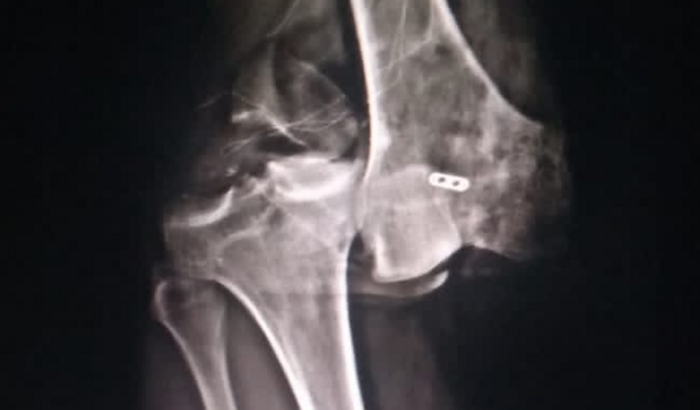

gente nosso amigo Suel, infelizmente sofreu um acidente de moto e acabou tendo uma fratura exposta com rompimento de ligamentos no joelho e precisa fazer uma cirurgia no valor de 30 mil reais com a fisioterapia, quem poder estar nos abençoando com qualquer quantia nos agradecemos, pois ele é quem sustenta sua família e está afastado devido a grave lesão .